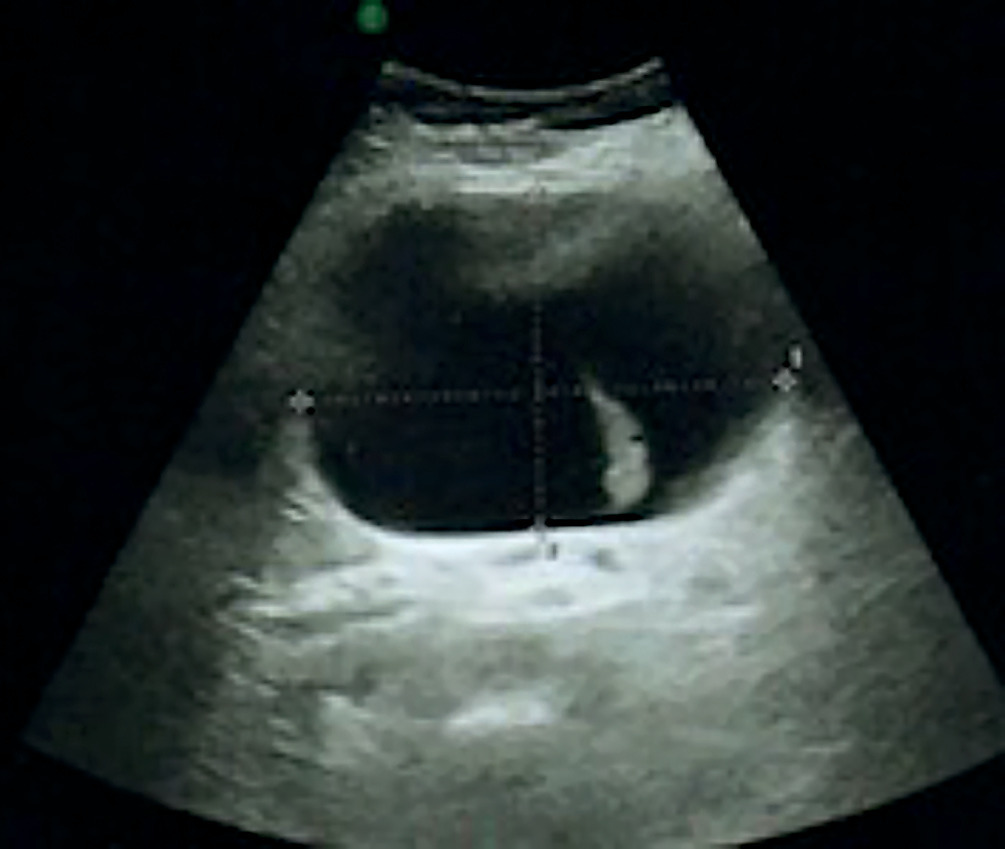

L’exploration biologique est strictement normale, sans cytolyse hépatique. L’échographie abdominale révèle un macrokyste de 10 cm à l’épigastre, contenant une cloison (fig. 1 ).

L’exploration biologique est strictement normale, sans cytolyse hépatique. L’échographie abdominale révèle un macrokyste de 10 cm à l’épigastre, contenant une cloison (

L’échographie est l’examen de référence dans les cas apparemment simples. Les kystes biliaires ont un aspect caractéristique : la lésion, ronde ou ovalaire, n’a ni paroi externe ni cloison interne, son contenu est anéchogène avec renforcement postérieur des échos.